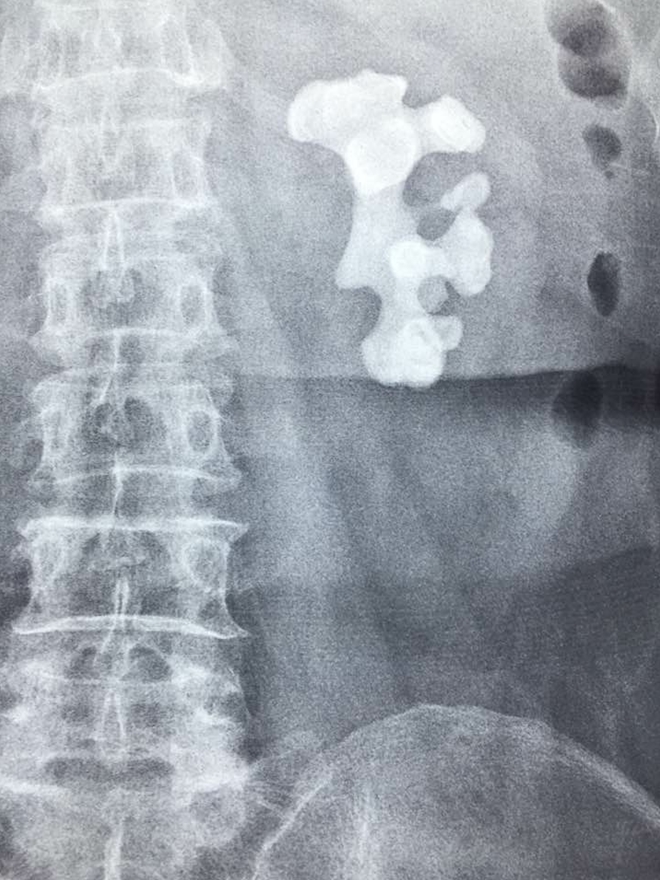

Hình chụp CT sỏi san hô

“Khi đến BV ĐHYD, sau khi thăm khám và chụp CT – scan, các bác sĩ trong Khoa Tiết niệu phát hiện người bệnh bị sỏi san hô kích thước 74mm x 48mm, chiếm hết toàn bộ thận và các đài thận.

Đây là 1 trường hợp sỏi thận phức tạp, hiếm gặp. Tên gọi sỏi san hô là do viên sỏi lấp đầy toàn bộ các nhánh đài thận, nhìn như một tảng san hô dưới biển. Nếu không điều trị sỏi sẽ tàn phá làm mất chức năng thận. Không phải chỉ vậy, sỏi này còn có thể gây ra những đợt nhiễm trùng thận tái đi tái lại, đôi khi nhiễm trùng nặng có thể gây nguy hiểm tính mạng”, ThS-BS Đức kể thêm.

Khu vực phát hiện sỏi san hô